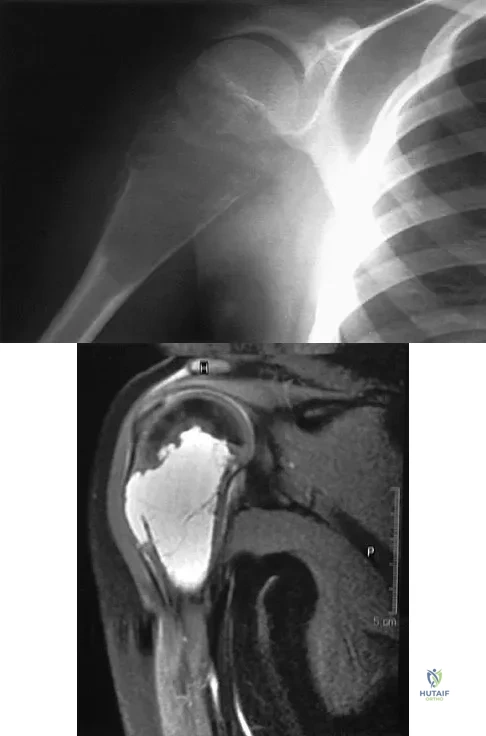

A 40-year-old right hand-dominant construction worker has had a 6-month history of aching left shoulder pain that is worse after working a long day. Examination reveals limited range of motion and good strength when compared to his asymptomatic right arm. He has not had any orthopaedic intervention to date. Radiographs are shown in Figures 43a and 43b. What is the most appropriate treatment?

Explanation